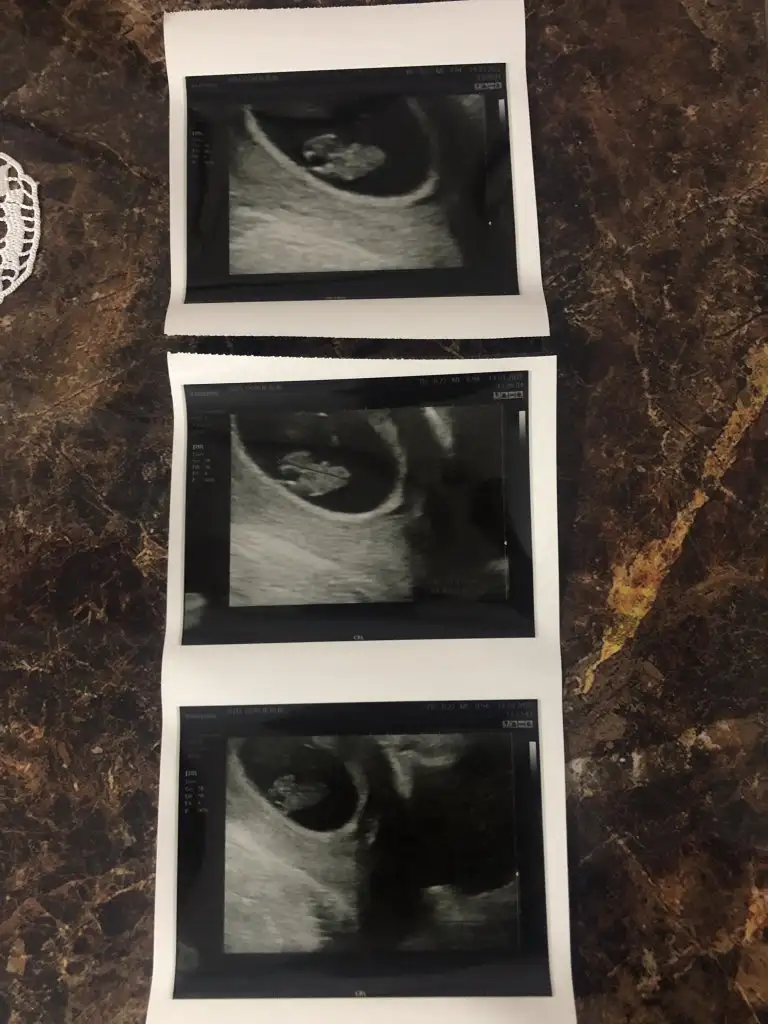

Şimdi ikisinin ayrı görüntülerini de atıyorum bi de böyle bakAnaaaaaaammmm bu ikinci keseyi 7+1 de mi gördün, ayy hep çok isterdim ikiz evladım olsun ne şanslın maşallahkuzu ikiside farklı cinsiyetler gibi duruyor biri kız biri erkek gibi. İlerleyen fotolarını da at emin olalım

kuzuuuu iki tosun paşa bunlarŞimdi ikisinin ayrı görüntülerini de atıyorum bi de böyle bakVajinal usg

kuzum karından bakılmıştır diye tahmin ediyorum. Tosun paşa gibi duruyor.Merhaba. Ultrason fotoğrafım tam 8 haftalıkken. Bana da tahminde bulunabilir misiniz acaba. Çok teşekkür ederim.